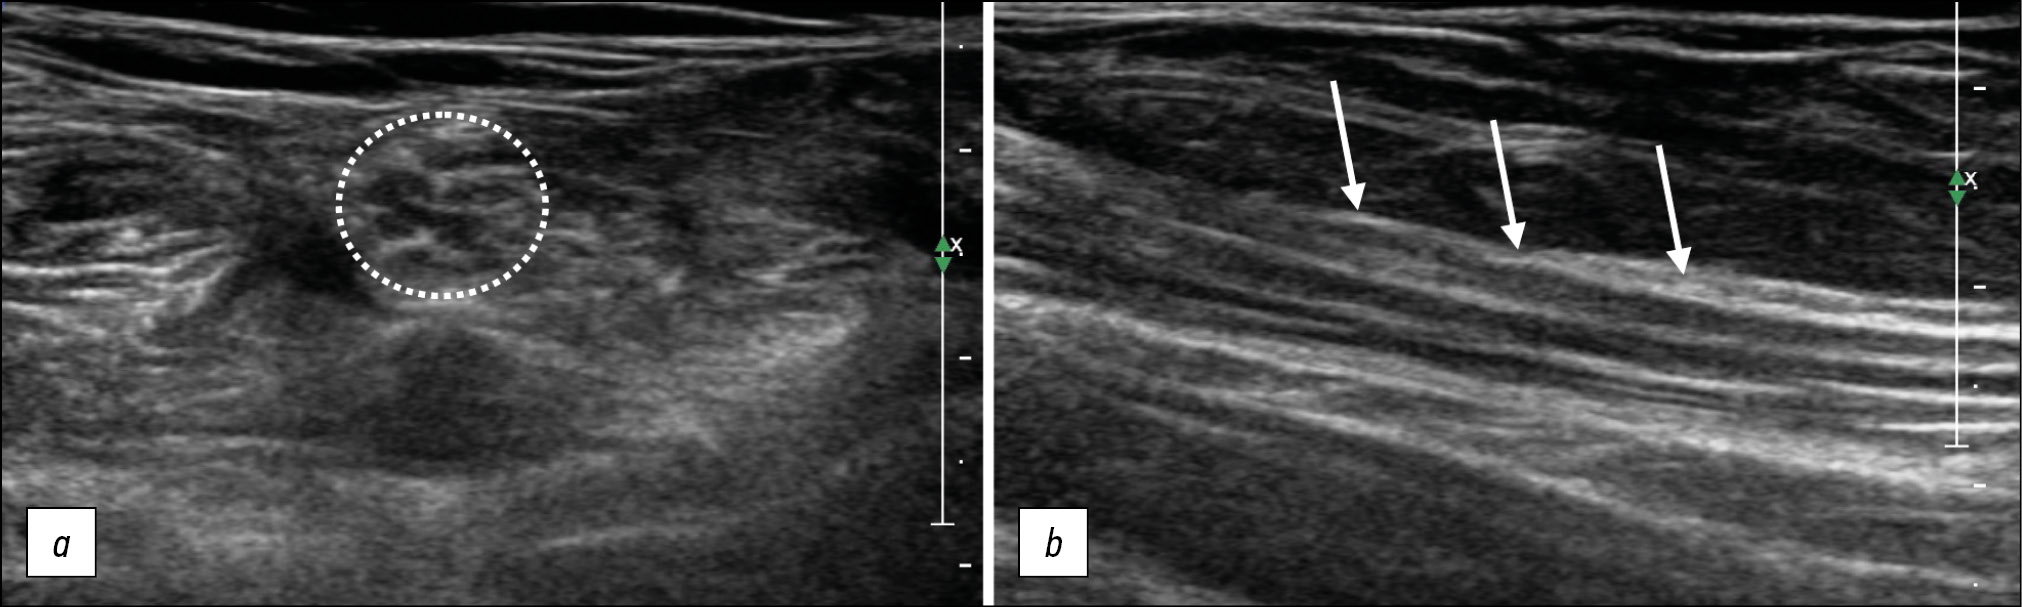

US is used to assess the volume (thickness) of muscle tissue for any muscle groups or individual muscles, to identify fibrotic changes, denervation processes (Fig. 3), as well as to determine the presence of spontaneous muscle contractions.

Fig. 3. Denervation changes in the quadriceps femoris muscle, longitudinal sonogram. (a) unchanged muscle, (b) denervated muscle: the muscle volume is reduced in volumewith increased echogenicity, and no differentiation of fibers.